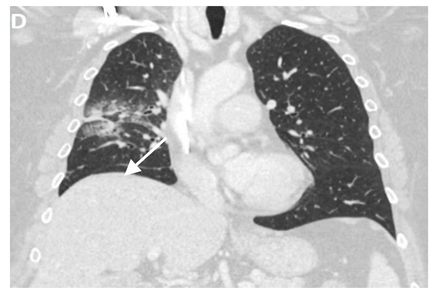

Even though X-ray is non-specific to pneumonitis, it is usually the first investigation performed. During the early phases, the most common finding on chest radiograph is perivascular haziness which frequently progresses to alveolar opacities [39]. Chest radiographs can show ground-glass opacity and/or consolidation in the radiation port. Consolidation usually has a nodular appearance but can be more confluent/lobar along with the irradiated port. Findings can be seen outside the radiation port as well. Some uncommon findings are ipsilateral pleural effusion with or without adjacent atelectasis [66]. Chest radiograph can also show bilateral interstitial infiltrates mimicking heart failure or acute respiratory distress syndrome (ARDS) [69,70]. All irradiated patients usually have some degree of abnormalities in the X-rays. Some fail to show any radiographic evidence of lung injury with pneumonitis. Early features exhibiting mild opacification of vascular markings are common, with later stages showing dense opacities. A radiographic straight-line effect may indicate the direction of the radiation port along the lines of pneumonitis [39,71] (Figure 1).

Figure 1.

Chest X-ray showing radiation pneumonitis Image 1—Frontal chest X-ray showing left upper lobe mass (arrow), the patient also had a right internal jugular port placed. Image 2—Post radiation treatment frontal chest X-ray showing increasing alveolar and interstitial opacities in the left upper lobe and in the left lower lobe in a patient suspected of radiation pneumonitis.

In the event of worsening symptoms after empirical antibiotics, Chest CT may provide more insights. Interestingly, the opacification lines in both X-ray and CT conform to radiation port rather than anatomical lines of lung structure, which could be diagnostic. Identified progression outside the lung field might suggest immune-mediated lymphocytic alveolitis [72]. Various stages of presentation provide different imaging outlooks (Table 3).

During the acute exudative stage, features of ground-glass attenuation or homogeneous consolidation may be noticed. A patchy consolidation that confirms the irradiation portal is also suggestive of the early phase. A discrete consolidation that conforms to the shape of the irradiation portal is proliferative changes of irradiation [71].

A chronic fibrosis stage with features of parenchymal distortion, traction bronchiectasis, and pleural thickening resulting in volume loss and irreversible changes are noticed. Refer to Table 2.